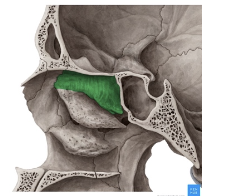

Lámina vertical del etmoides

Lámina perpendicular del etmoides

Forma parte del tabique de separación de ambas fosas nasales (septum/tabique nasal)

Apófisis crista galli por arriba de la lámina horizontal

Apófisis crista galli

Triangular, borde anterior bajo articula con el hueso frontal y completan el agujero ciego(foramen cecum) entre surcos